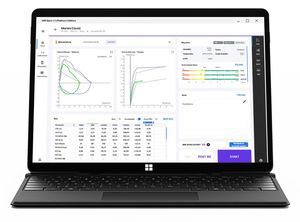

... ¡Disfruta de tu experiencia Platinum! - Software integral para Espirometría y Oximetría: MIR Spiro Platinum ofrece una suite completa para espirometría y oximetría, apoyando a los profesionales de la salud y a los pacientes en la gestión ...